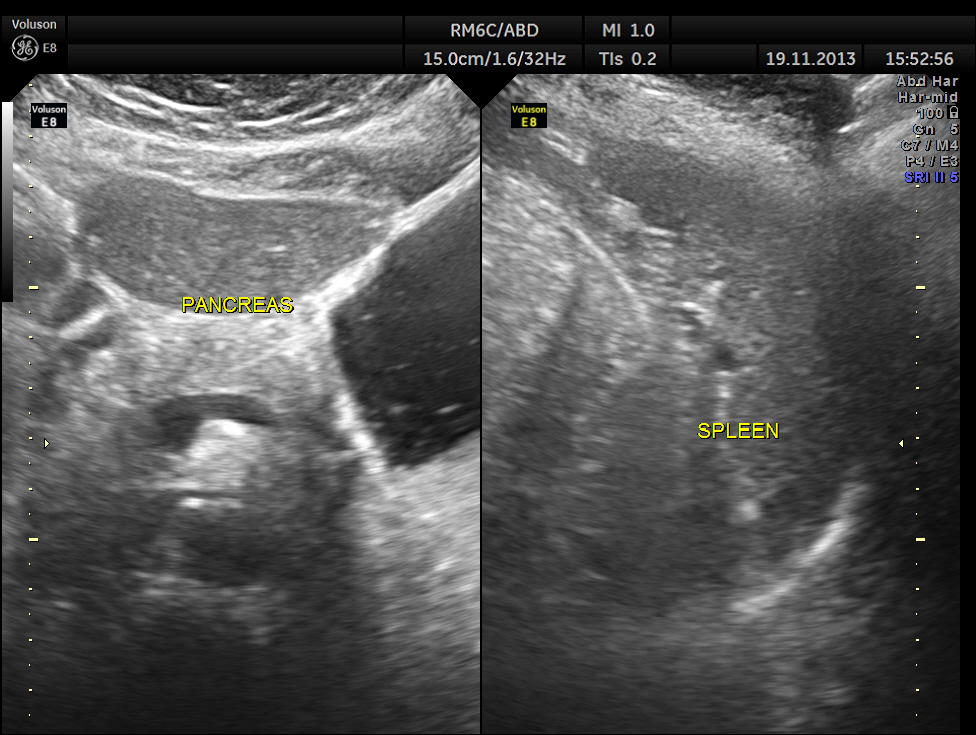

Her abdominal scan revealed a distended gall bladder with two big gallstones and one of them was obstructing the cystic duct.